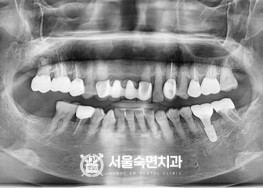

임플란트-치료-전후사진